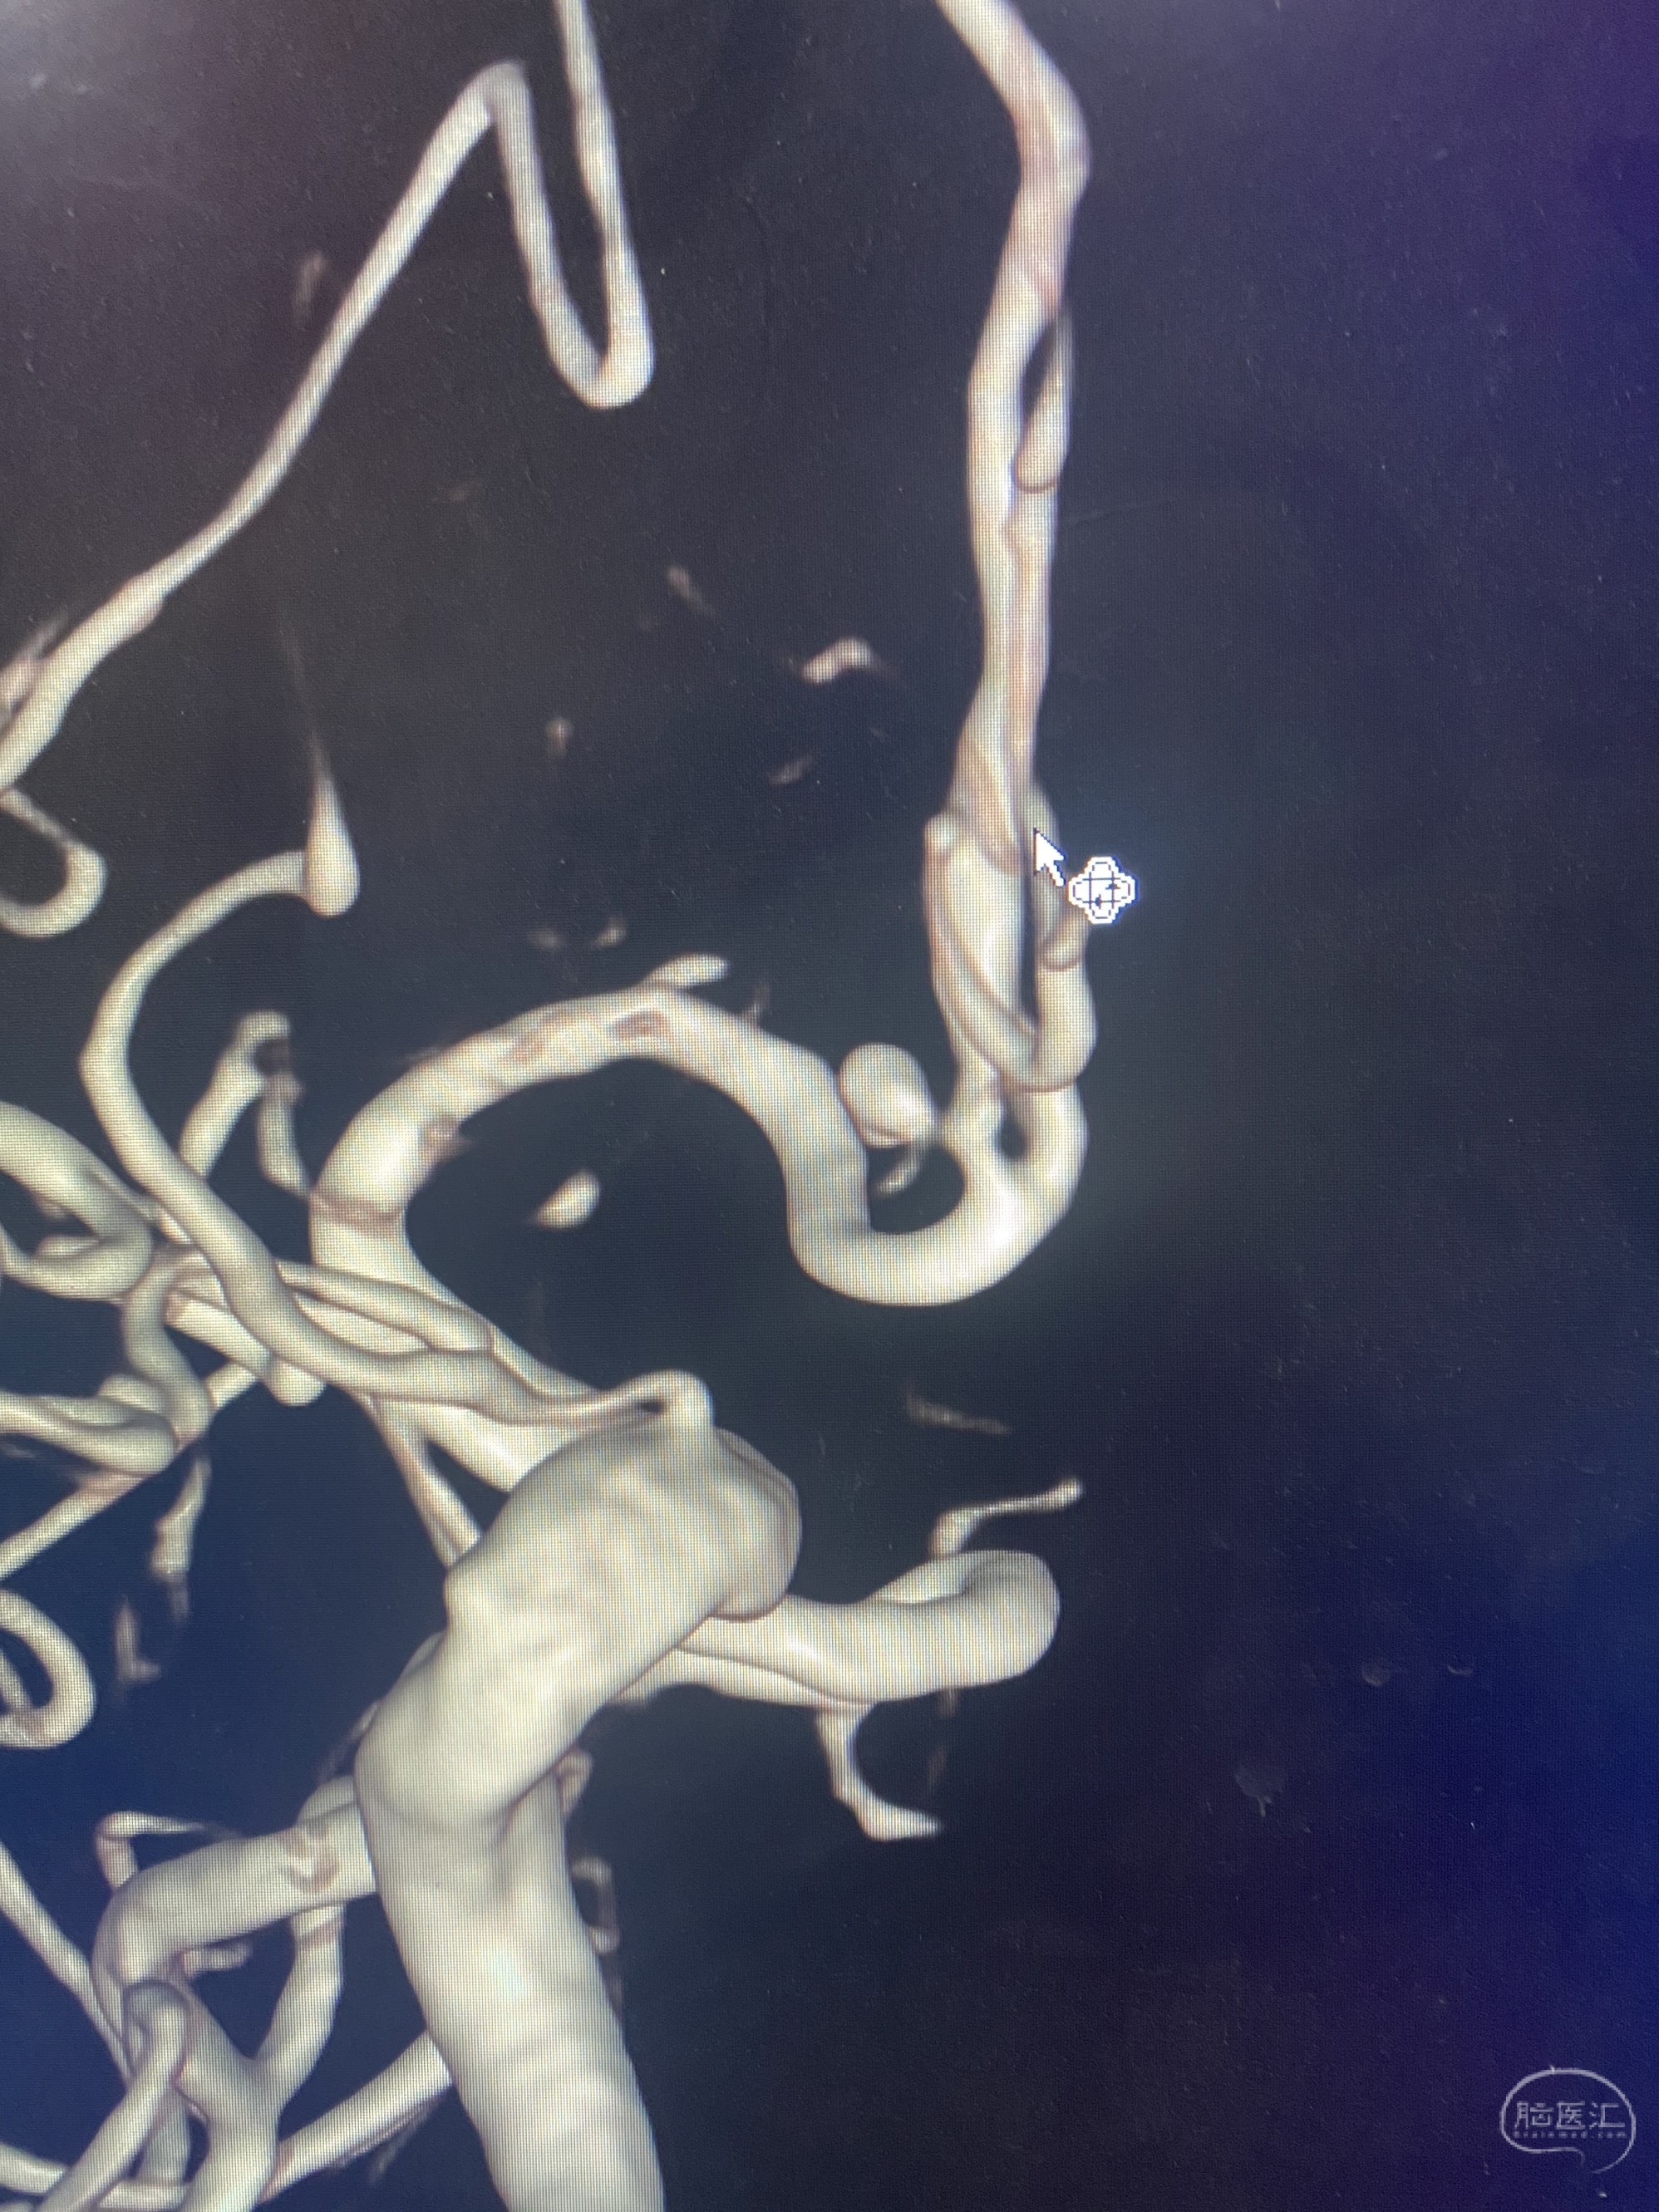

MLS,M79Y,sah,双侧MCA烟雾病,Heubner返动脉瘤,前交通段开窗,细支发出Heubner返动脉,瘤颈细长,瘤颈口比微导管细,弹簧圈2mmx3cm“隔山打牛”填塞治愈,Heubner返动脉保留。

Heubner返动脉是由大脑前动脉A1末端发出的豆纹动脉,由于走形和A1段相反,故称Heubner返动脉,该动脉梗塞可能引起尾状核头梗塞,引起偏瘫和面瘫,便身震颤等症状。